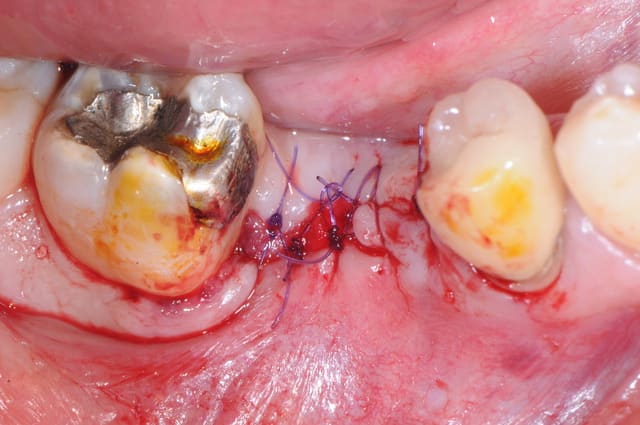

il y a eu comblement osseux avec biooss et mise en place de mucograft seal (peu visible sur la photo) même si c'était PRESQUE pas nécessaire (bretelle et ceinture)